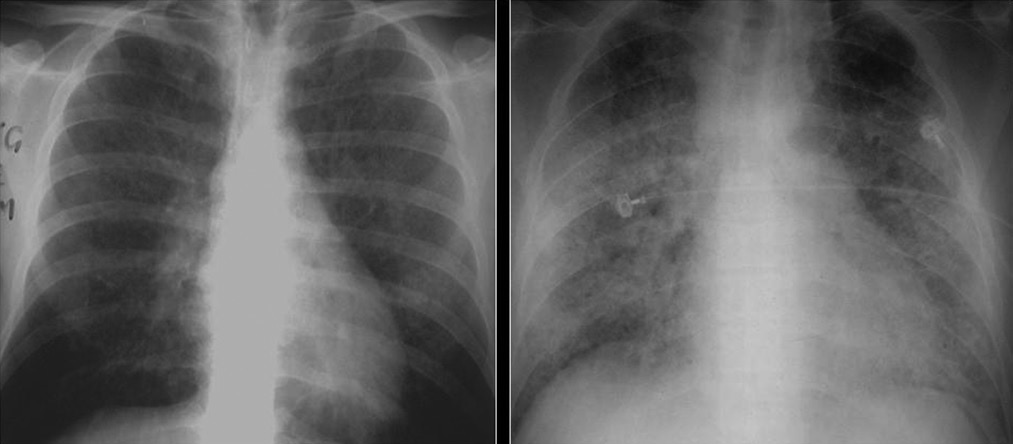

Difference Between Lung Infiltrate and Consolidation

When we breathe in, the inhaled air enters the trachea, the branches, and through progressively smaller airways reaches the alveoli – microscopic bubbles, where the gas exchange occurs. In some cases, the alveoli can fill up with a substance, for example with pus (e.g. in pneumonia), protein (in certain rare lung diseases), blood, water (e.g. pulmonary edema), cancer cells, etc. This substance is called lung infiltrate. The alveoli filled with infiltrate can be seen on a chest X-ray as an area, denser than the surrounding lung tissues, called consolidation.

What is Lung Consolidation?

The region of the lungs where the alveoli are filled with an atypical substance (i.e. lung infiltrate) instead of air is called lung consolidation. It is marked by hardening or swelling of the lung tissue and obstruction of the aeration in the affected area of the lung. Consolidation occurs in different diseases (when lung infiltrate occurs) and is an important radiologic sign.

Depending on the severity of the condition, the consolidation can cover a very small area of the lung surface and cause minimal symptoms, or cover a large part of the lung and cause a life-threatening condition.

Some of the common causes of consolidation are pneumonia, pulmonary edema, and pulmonary hemorrhage.

Pneumonia is the most common cause of lung consolidation. When there is an infection in the lungs, the body sends white blood cells to fight it. Dead cells and debris accumulate, creating pus that fills the small airways. Pneumonia is usually caused by bacteria or viruses, but can also be caused by fungi or other causes.

Congestive heart failure is the most common cause of pulmonary edema. When the heart cannot pump enough to keep the blood moving, it returns to the blood vessels in the lungs. The increased pressure pushes fluid out of the blood vessels into the small airways.

Pulmonary hemorrhage is most often caused by vasculitis (inflammation of the blood vessels), which makes the blood vessels weak and causes blood to pass into the small airways.

[3]Image credit: https://commons.wikimedia.org/wiki/File:X-ray_lung_consolidation.jpg

[4]Image credit: https://commons.wikimedia.org/wiki/File:X-ray_of_ground_glass_opacities_of_pneumocystis_pneumonia.jpg